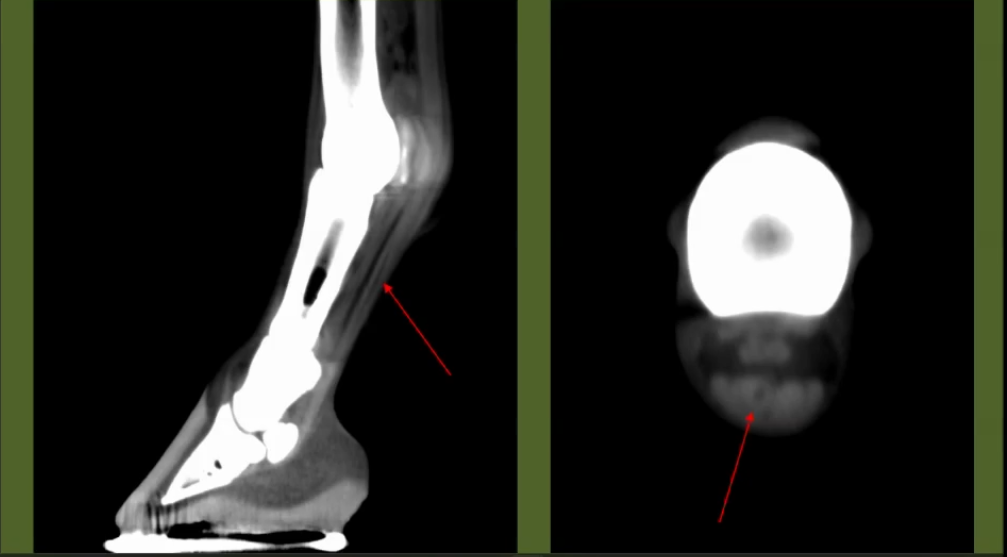

STANDING LIMB IMAGING